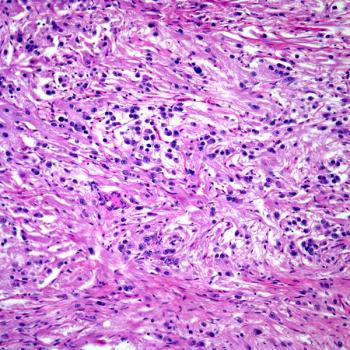

A 36-year-old man presents with a painless right arm mass. What is your diagnosis?